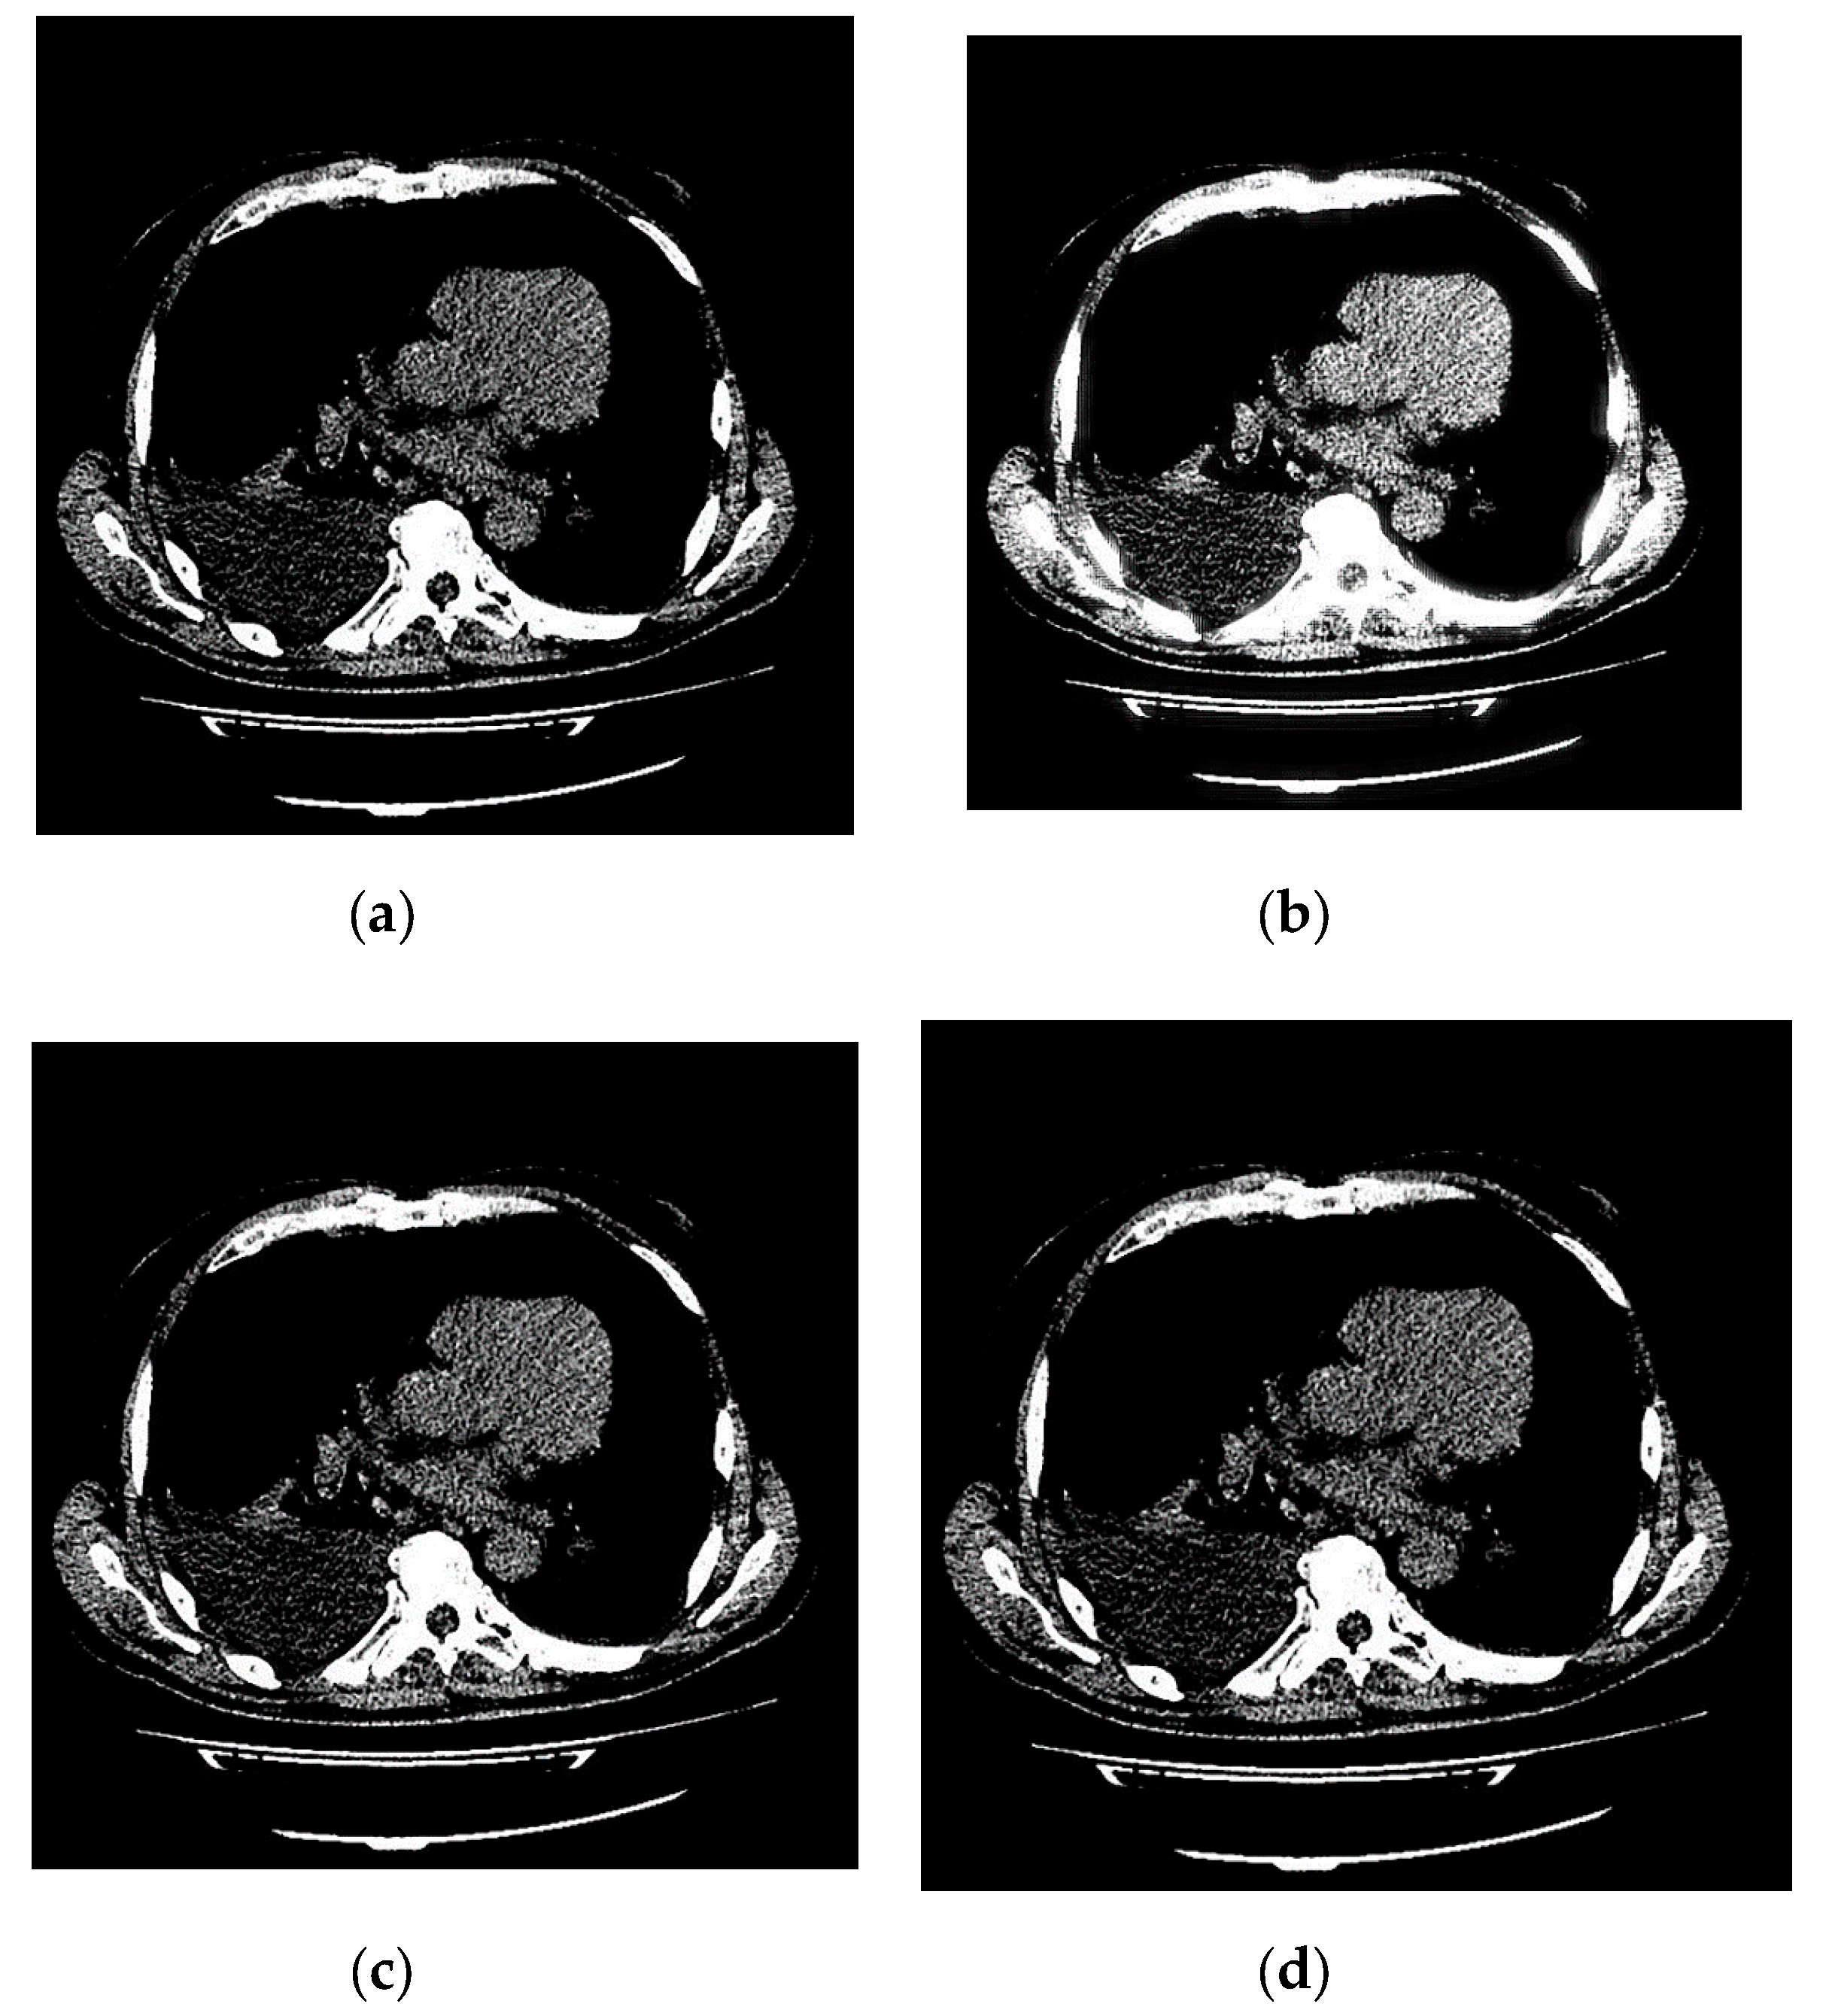

Experimental results (, dB) of various 3D tomographic 12-bit grayscale images DWT by wavelet with bit-width of filters coefficients are presented in Table 34 and in Figure 8.

Figure 8.

Experimental results of 3D tomographic 12-bit images DWT by wavelet with bit-width of filters coefficients.

The nonlinear hyperbolic regression [53] curve for the data from Table 34 was plotted in Figure 8 and has the equation , where is the average brightness of the image voxels. The -test value [54] for constructed nonlinear hyperbolic regression curve is actually observed. The -test critical value [55] for false-rejection probability with degrees of freedom and is , where is the regression equation estimated parameters number and is the images number from Table 34. Since resulting regression equation is significant at false-rejection probability . Equation asymptote exceeds the corresponding theoretical calculations values.